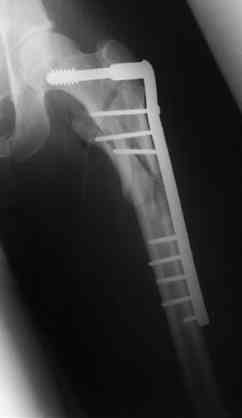

Бедро фиксировал длинной DCS.

По типу бриджинг плэйтин, крюком удалось низвести малый вертел и фиксировать винтом для восстановления медиальной стенки.

> Бедро фиксировал длинной DCS.

А почему не гвоздем закрыто?

ET>> Бедро фиксировал длинной DCS.

AC>А почему не гвоздем закрыто?

Изначально планировался длинный гамма гвоздь , но набор заказывается обычно из Йоханнесбурга, а в этот раз все совпало с новогодними празднованиями и вся жизнь была *парализована* новогодней фиестой:-((, поэтому безуспешно прождав 3-4-5 дней обещанной доставки зафиксировал пластиной- жаль, что так всй случилось У местного

Страйкера сервис ненавязчивый :-))

В приложении отправляю послеопер. снимки бедра и лодыжки обсуждаемого вчера больного.